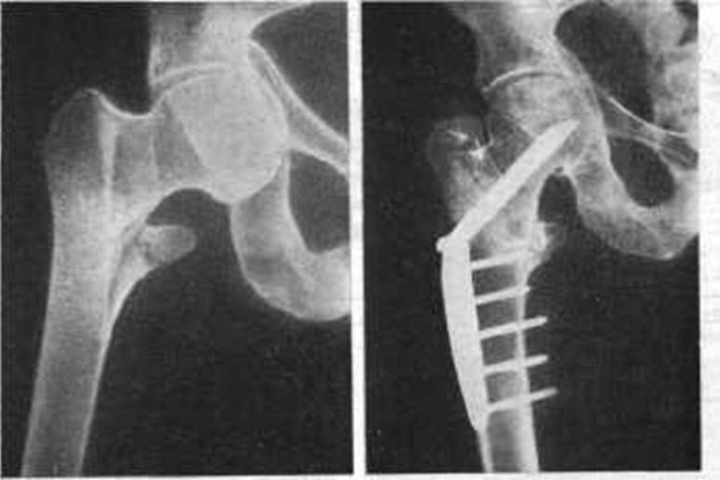

Перелом Бедра Фото Рентген

Перелом Бедра Фото Рентген 138 фото